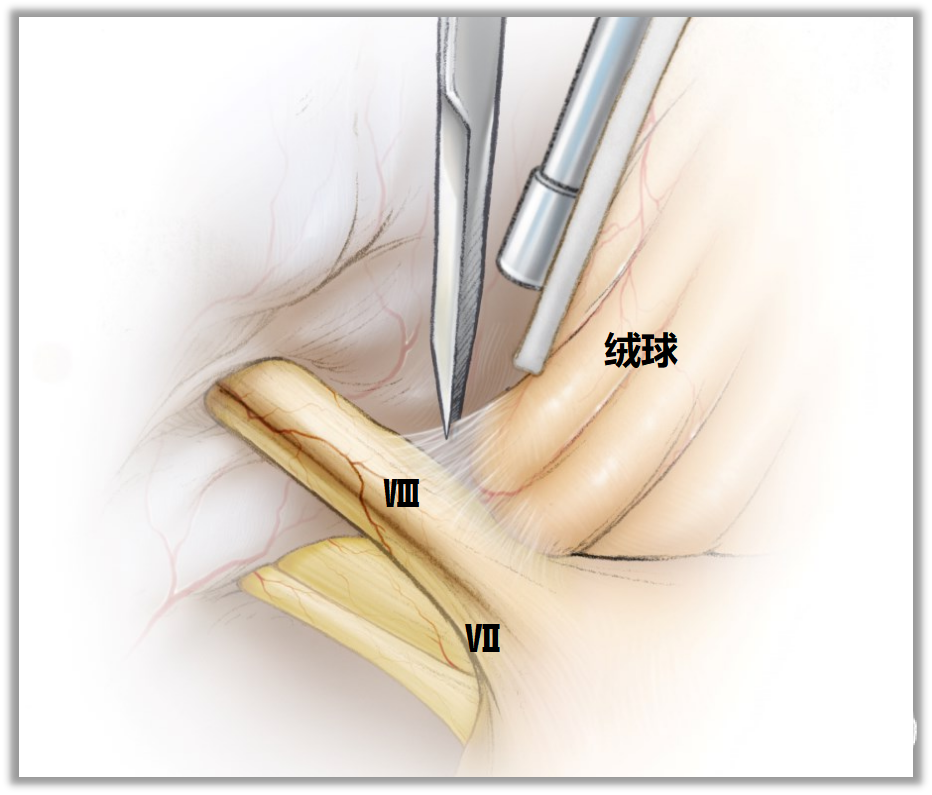

▼15.小脑绒球下入路

小脑绒球下入路(infrafloccular approach)最早由日本专家Matsushima提出。因为绒球和从Luschka孔突出的脉络丛从外侧遮挡面神经REZ区(下图),而且,在绒球和前庭蜗神经之间经常有黏连,还可能存在大量坚韧的蛛网膜小梁,因此从小脑外侧间隙很难暴露REZ区,还可能造成听力损伤。

此时重要的是要牢记面神经出脑干处位于舌咽神经入脑干处上方2~3mm。

绒球下入路(上图)就是抬起小脑的下外侧缘,打开舌咽神经和迷走神经后方的蛛网膜,便可暴露由Luschka孔突出的位于舌咽神经和迷走神经后面的脉络丛,将脉络丛从舌咽神经后缘轻轻分开,以暴露舌咽神经与脑干连接处。脑板进一步向上将脉络丛从舌咽神经后缘上抬起,暴露范围向舌咽神经上方扩展数毫米,此处即为面神经与脑干的连接处(REZ区),恰位于前庭蜗神经的前下方。